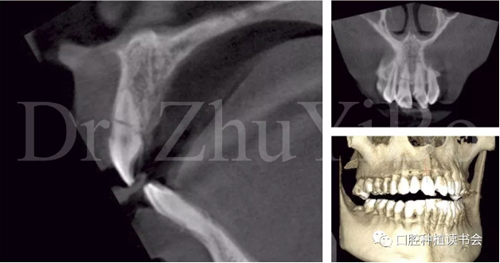

術前cbct顯示:右上中切牙牙根牙槽突類型為一型(圖8)。牙齦為厚型牙齦類型;咬合關系基本正常。

圖8 CBCT:11可見明顯根折線,無法保留

圖15術后即刻CBCT示:種植體軸向及深度良好